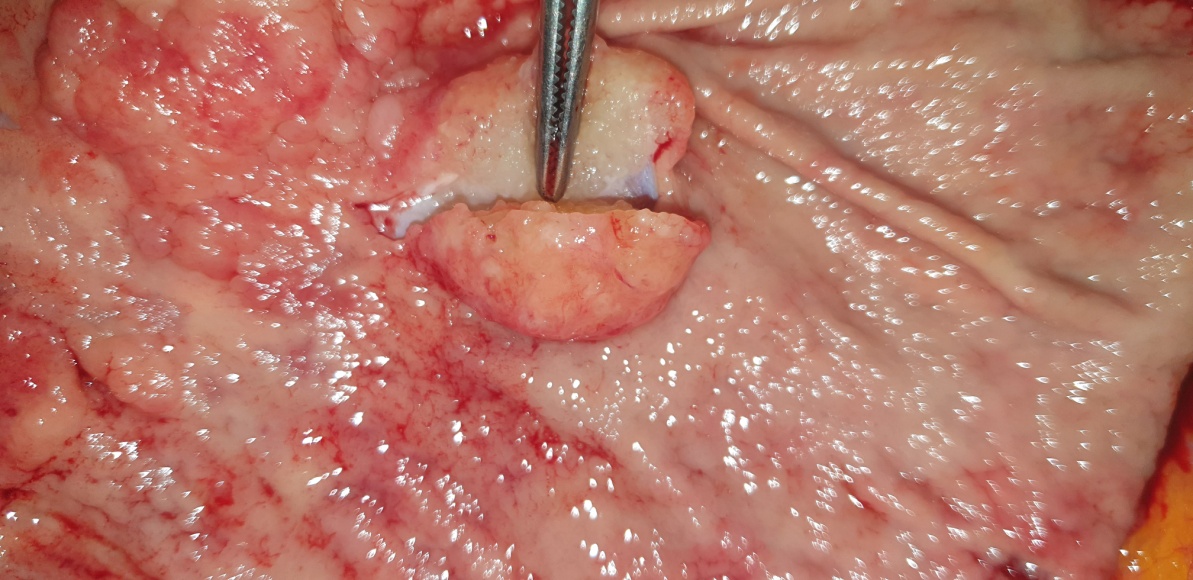

Anatomical forceps within the fistula orifice in the duodenum (Courtesy Dr. V. Penopoulos)